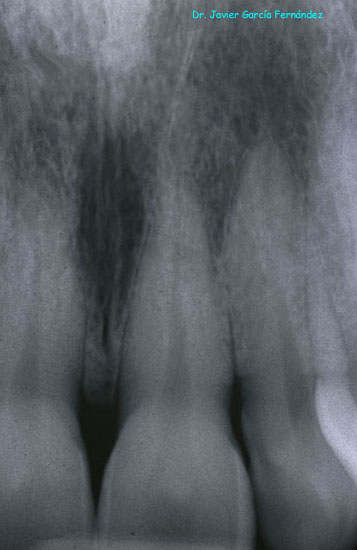

image005